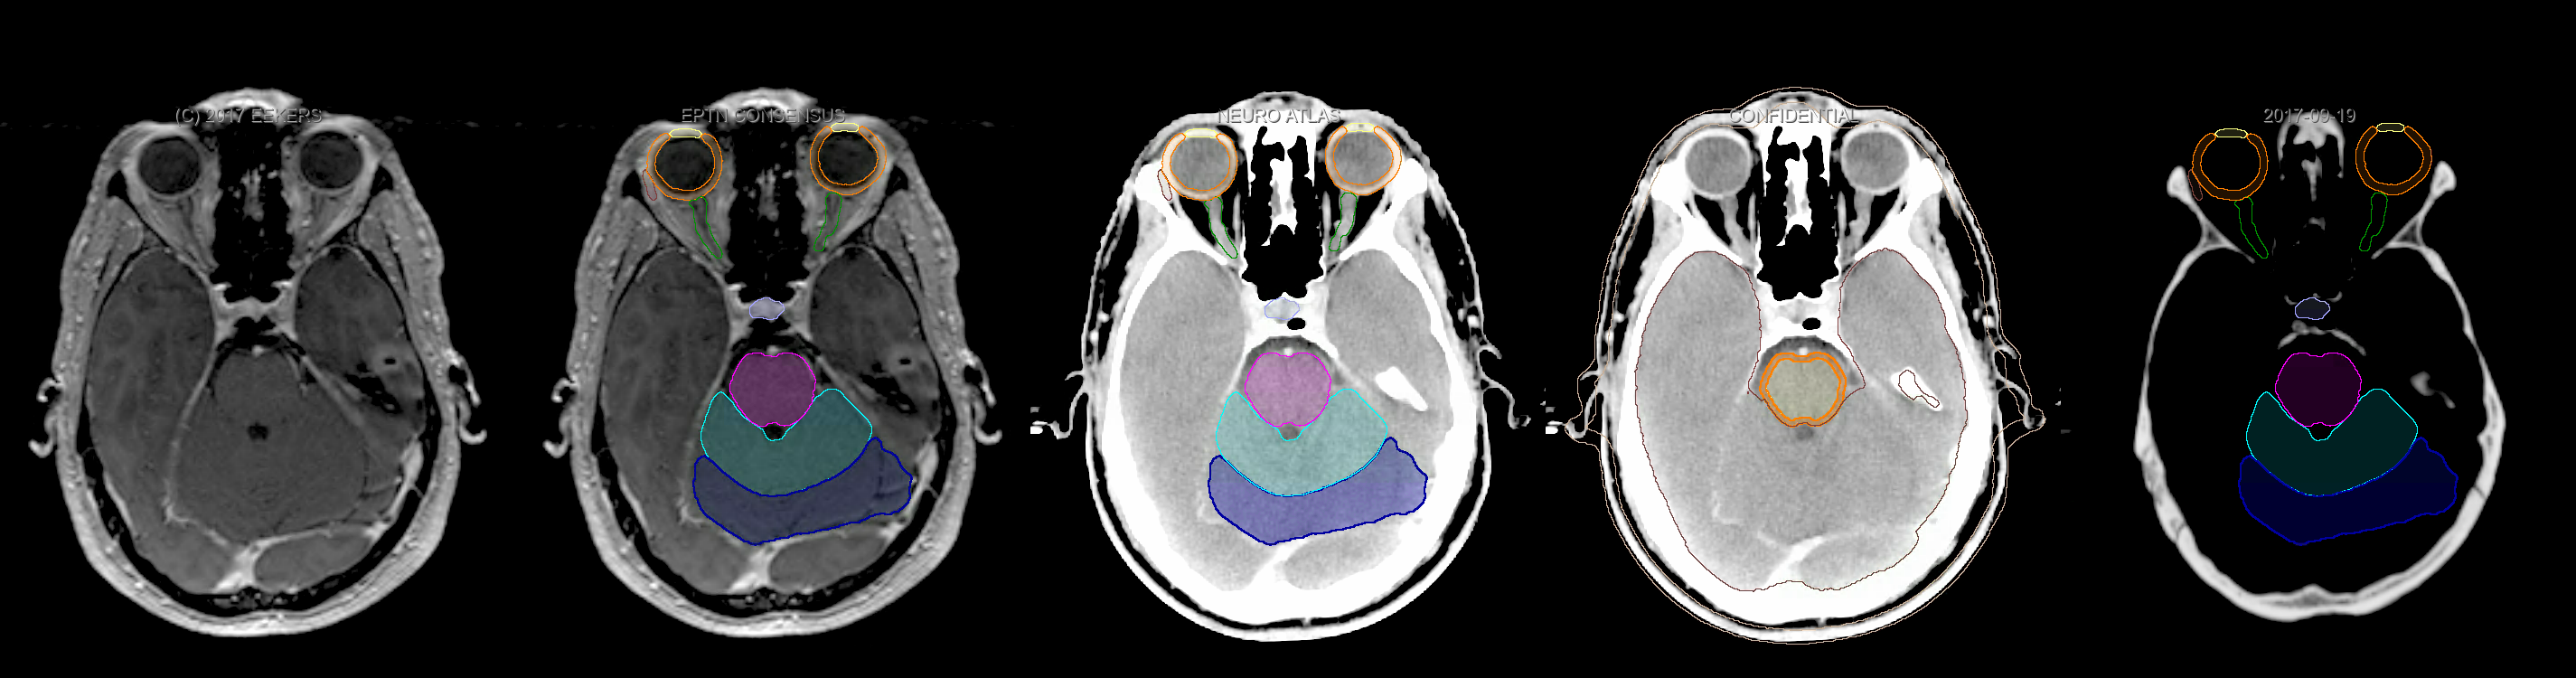

Three-dimensional delineation of the fifteen consensus OARs for neuro-oncology are shown on CT and 3 Tesla (3T) MR images (slice thickness 1 mm with intravenous contrast agent). All are presented in transversal, sagittal and coronal view.

From left to right: MR without structures, MR with structures, CT (WW/WL 120/40) with structures, CT (WW/WL 120/40) with Brain and Brainstem Surface, CT (WW/WL 1500/120)with structures